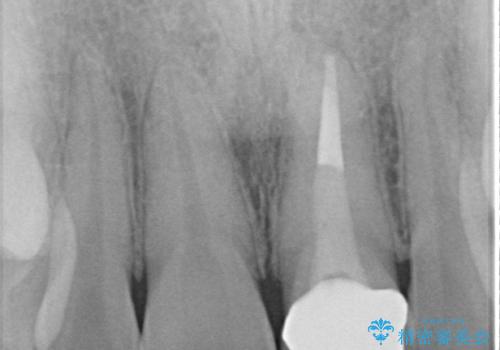

- 以前装着された前歯のかぶせ物の色を変えたいとのことで来院されました。

土台からの再治療を行い、オールセラミッククラウンを装着する治療計画としました。